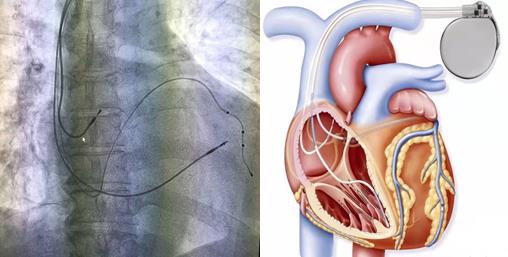

新跳動(dòng)、新同步、“心”希望——延安大學(xué)咸陽(yáng)醫(yī)院心血管內(nèi)科三病區(qū)成功獨(dú)立完成虎年首例三腔起搏器植入術(shù)

近日,延安大學(xué)咸陽(yáng)醫(yī)院心血管內(nèi)科三病區(qū)蔡萍主任醫(yī)師介入團(tuán)隊(duì),成功獨(dú)立完成虎年首例三腔起搏器植入術(shù)。為心肌病、重度心衰、心功能不全患者的治療提供了一個(gè)新的保障。

患者64歲、女性、以“反復(fù)胸悶、氣短20天”之主訴入當(dāng)?shù)蒯t(yī)院,期間多次發(fā)生急性心功能不全,行心臟彩超示:EF:36%,左心房、左心室大,心電圖示:竇性心律 III°房室傳導(dǎo)阻滯(QRS波150ms)。當(dāng)?shù)蒯t(yī)院行CAG術(shù):血管未見(jiàn)明顯狹窄。診斷:擴(kuò)張型心肌病 III°房室傳導(dǎo)阻滯心功能IV級(jí)。在臨時(shí)起搏器保駕下轉(zhuǎn)入我科進(jìn)一步治療。

考慮到患者目前存在心功能不全,且新四聯(lián)藥物治療后效果欠佳,植入傳統(tǒng)雙腔起搏器完全右室起搏可能會(huì)導(dǎo)致心功能惡化,且2021年ESC指南也將這類患者CRT(心臟再同步化治療)適應(yīng)癥由2013年ESC指南 IIa推薦升級(jí)為I類推薦。經(jīng)全科醫(yī)生討論下,決定為患者行三腔起搏器植入術(shù)。

手術(shù)過(guò)程:手術(shù)開(kāi)始,患者在局部麻醉下,順利穿刺左側(cè)腋靜脈成功后,依次植入右室主動(dòng)電極、過(guò)鞘管送遞長(zhǎng)鞘、沿長(zhǎng)鞘送十極至冠狀動(dòng)脈竇口,推送進(jìn)冠狀竇遠(yuǎn)端,沿十極電極遞送長(zhǎng)鞘至冠狀竇,取出十極電極,在雙導(dǎo)絲支撐下送造影球囊進(jìn)行造影,選擇合適的心左側(cè)靜脈后,順利植入左室電極,再植入右房主動(dòng)電極,多體位投照各電極位置合適、測(cè)試起搏參數(shù)均符合要求,遂固定電極后植入起搏器。歷經(jīng)2.5小時(shí), 三腔起搏器植入術(shù)順利完成,患者各項(xiàng)參數(shù)檢測(cè)均正常。

目前常用的“單(雙)腔心臟起搏器”均只能治療心動(dòng)過(guò)緩,但三腔起搏器可實(shí)現(xiàn)心臟再同步化治療(CRT)目的,不但具有治療心動(dòng)過(guò)緩的功能,還能解決由于患者左右心室收縮不同步而導(dǎo)致的心衰癥狀。它是在傳統(tǒng)的雙腔起搏(右心房,右心室起博)的基礎(chǔ)上增加了左心室起搏,左室起搏電極經(jīng)右房的冠狀靜脈竇開(kāi)口,進(jìn)入冠狀靜脈左室后側(cè)壁支起搏左室,通過(guò)多部位起搏恢復(fù)左右心室同步收縮,增加左心室充盈時(shí)間,減少室間隔矛盾運(yùn)動(dòng),減少二尖瓣返流,從而改善患者的心臟功能,甚至可以讓擴(kuò)大的心臟回縮,提高運(yùn)動(dòng)耐量以及生活質(zhì)量。

CRTD是心臟再同步化治療合并有除顫功能的起搏器的英文縮寫,它結(jié)合了心臟再同步化治療(CRT)和埋藏式心臟復(fù)律除顫器(ICD)的雙重功能,可自動(dòng)監(jiān)測(cè)心律失常,并具有自動(dòng)除顫功能,相當(dāng)于把“心臟監(jiān)護(hù)室”置入心臟里面一樣,再實(shí)現(xiàn)左右心室同步收縮,改善心功能同時(shí),能夠防治惡性心律失常導(dǎo)致的猝死。